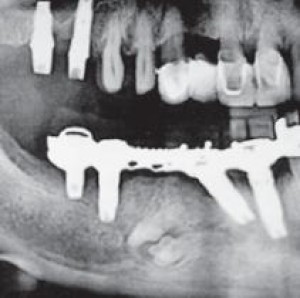

ObiettiviObiettivo del presente lavoro è illustrare l'utilizzo del pericranio a copertura di un innesto di calvaria nella ricostruzione di una mandibola gravemente atrofica, a scopo...